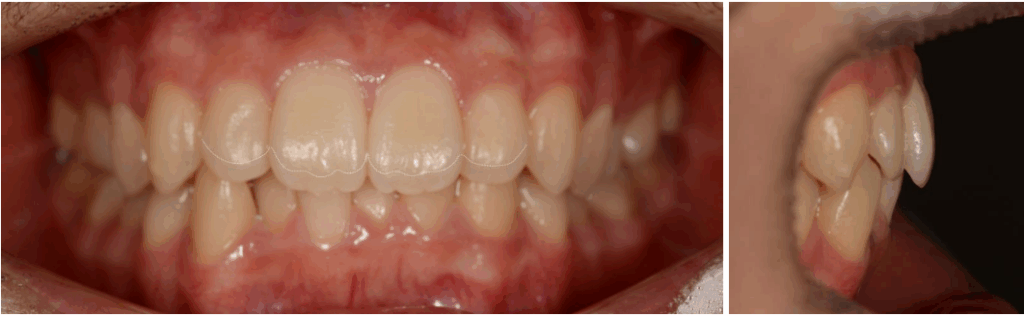

25.03.07

치료 후 모습을 보면

위아래 전치부 덧니와

이소맹출 어금니가 개선되었으며,

윗니가 아랫니를 과하게 덮고 있는

과개 교합이 해결되었습니다.